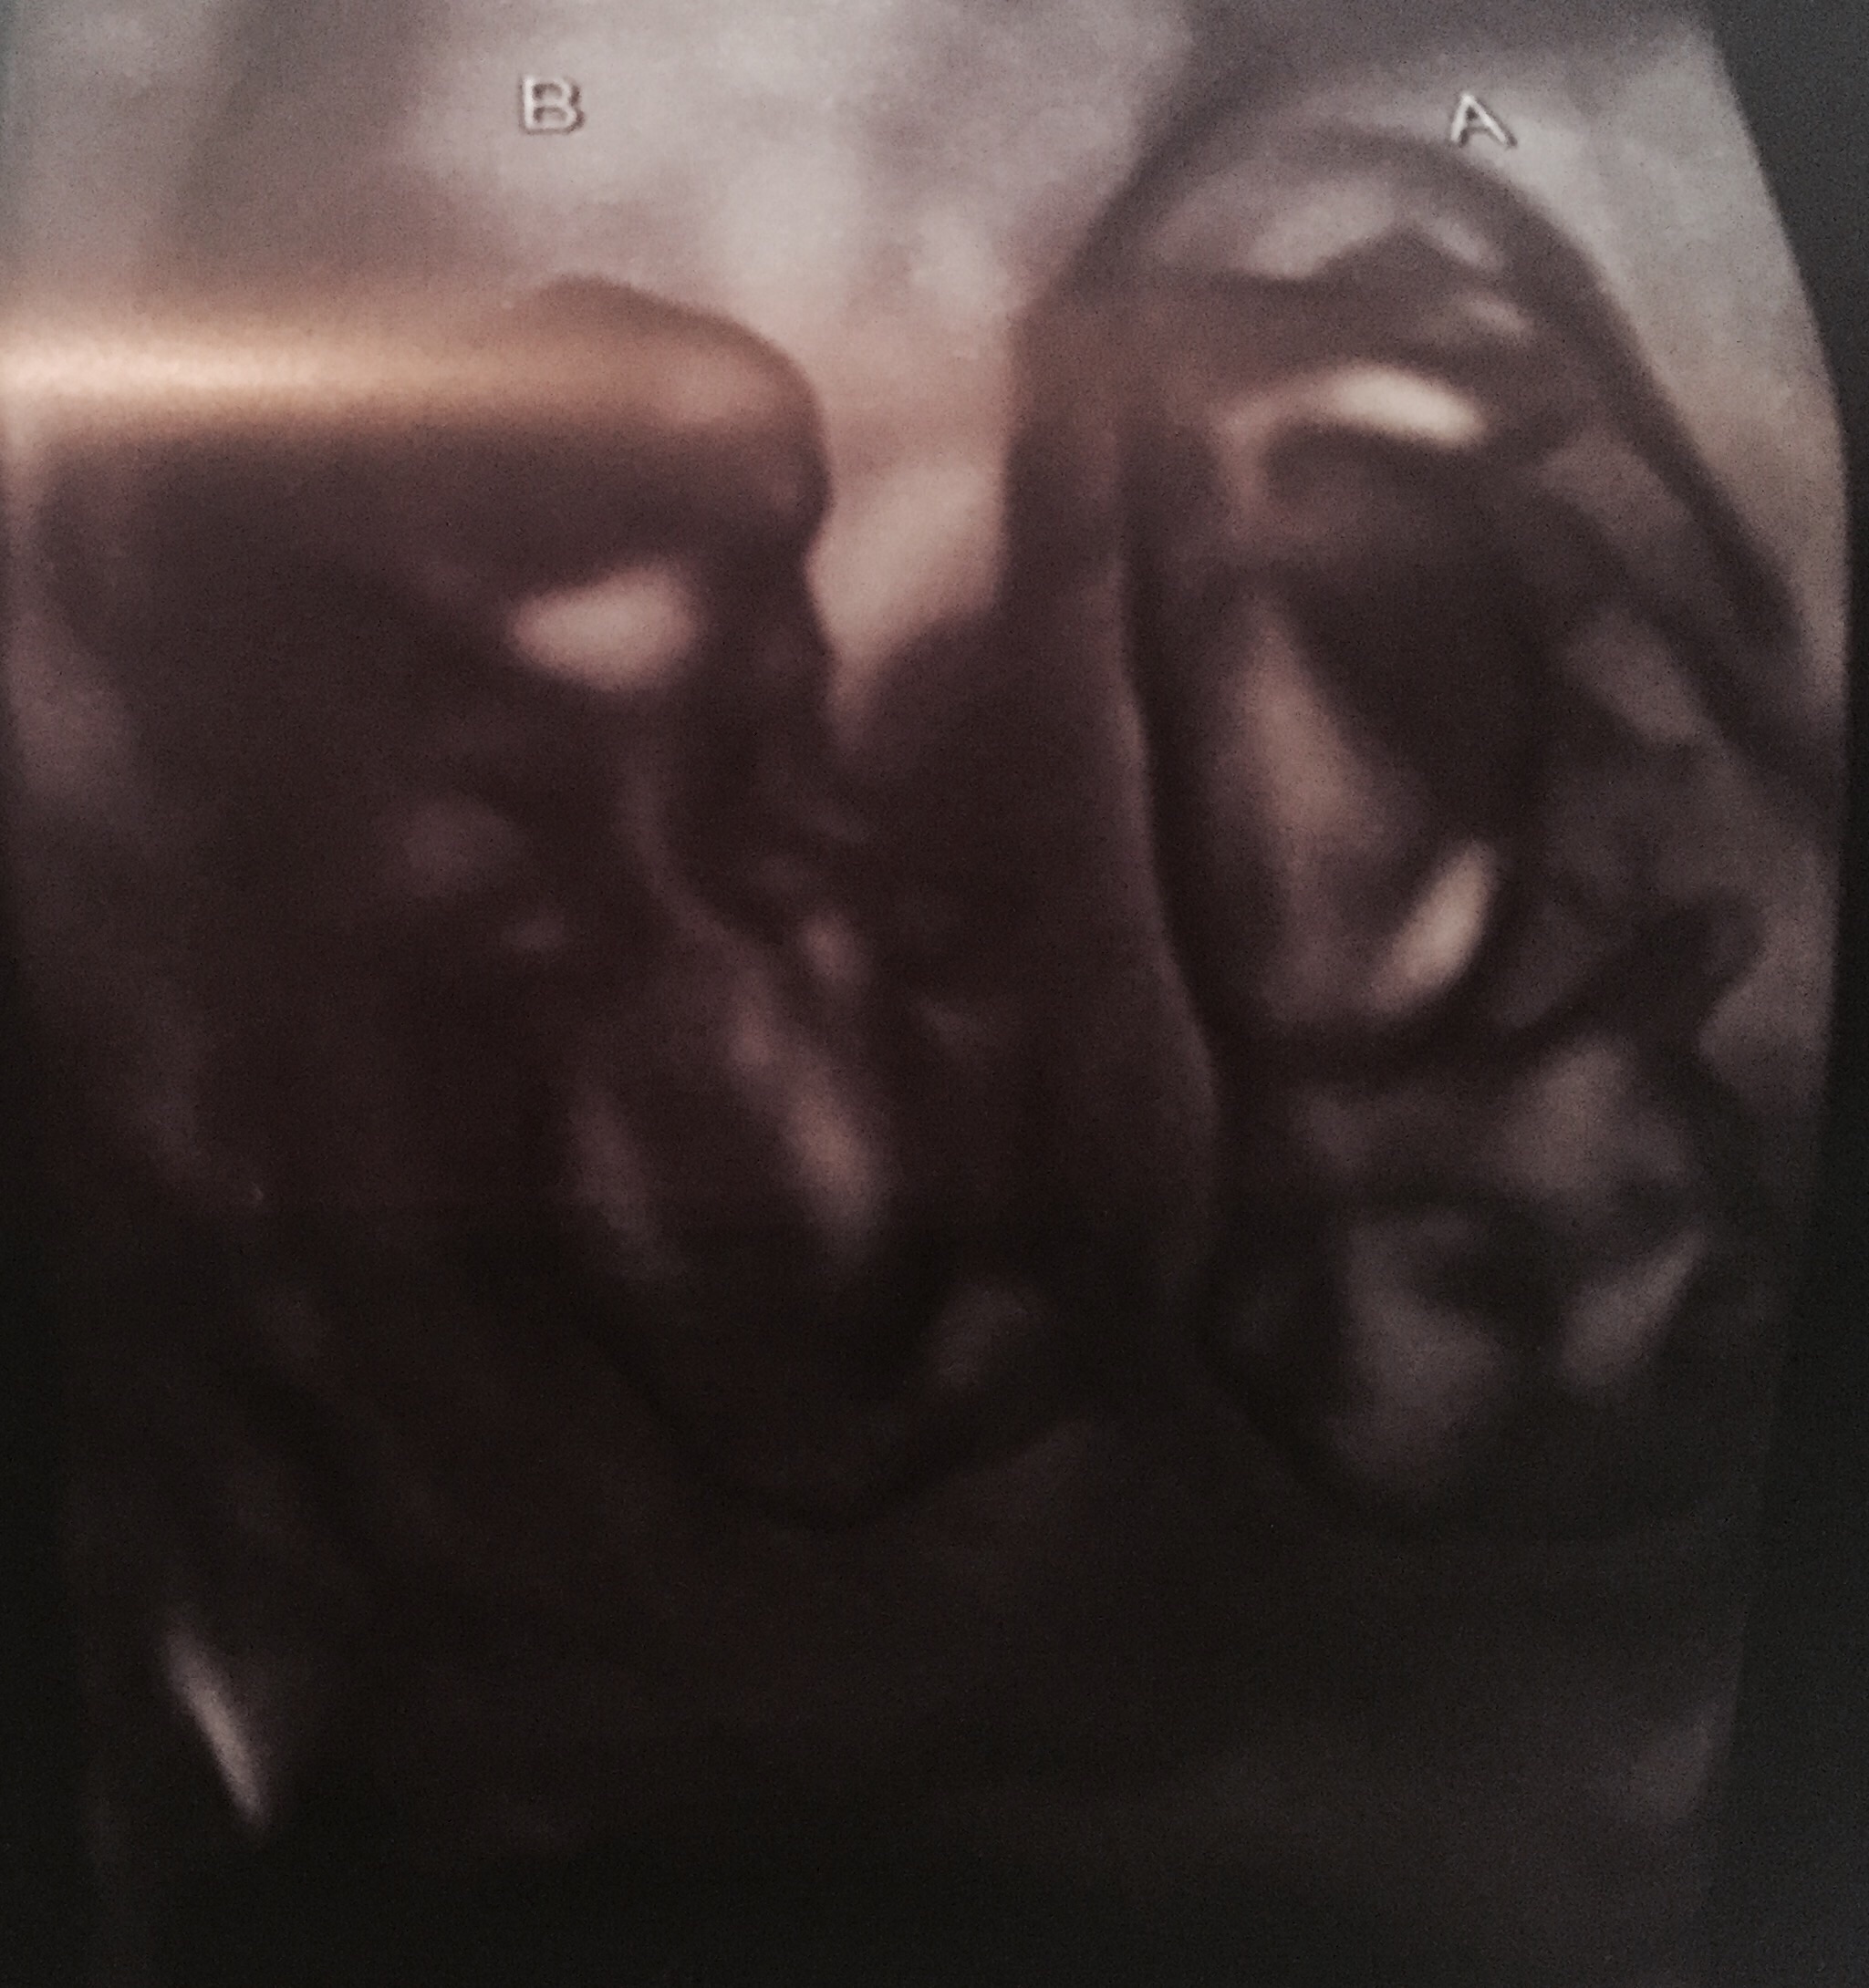

Here are my twins from my 13 week ultrasound. Both have strong heartbeats! One measuring at 13 weeks 4 days and the other 13 weeks 6 days. Tech made a guess and thinks they're boys!!